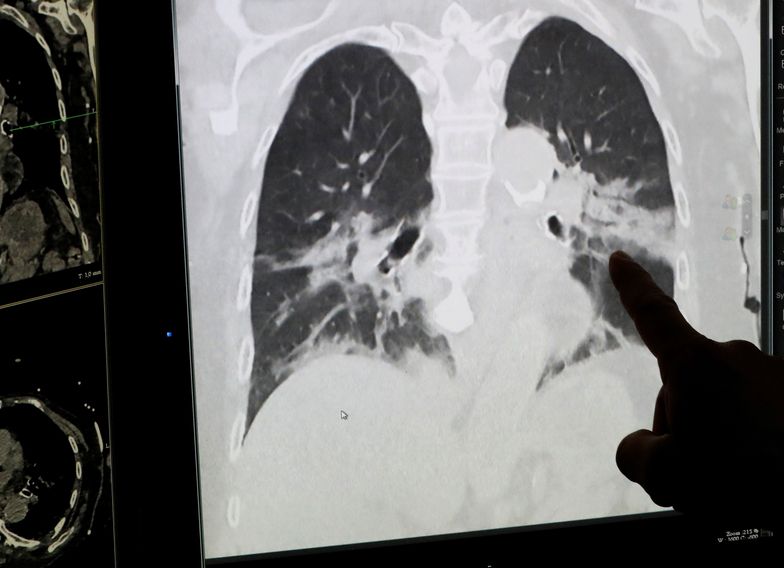

’Lekarze z Kliniki Uniwersyteckiej w Innsbrucku (Austria) przebadali sześć osób wyleczonych z COVID-19. Mimo że wszyscy przeszli chorobę łagodnie, to zauważono u nich poważne i nieodwracalne uszkodzenia płuc.’

Koronawirus stanowi poważne zagrożenie dla płuc.